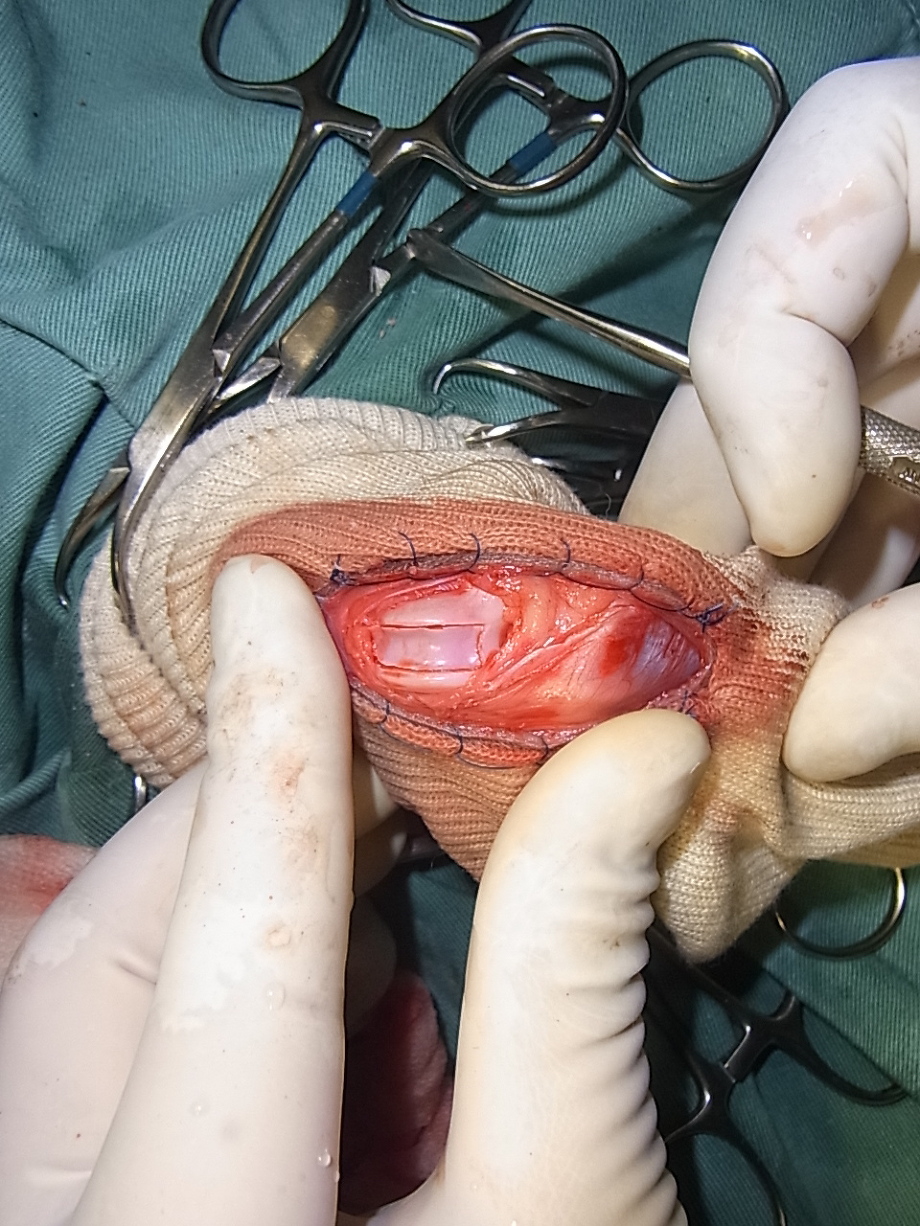

関節包を縫合したところです。関節包は強度があまりありませんので縫縮する必要はありません。

外側の筋膜を鱗状に被せ膝蓋骨を覆うように縫合し外側にテンションがかかるように縫縮します。